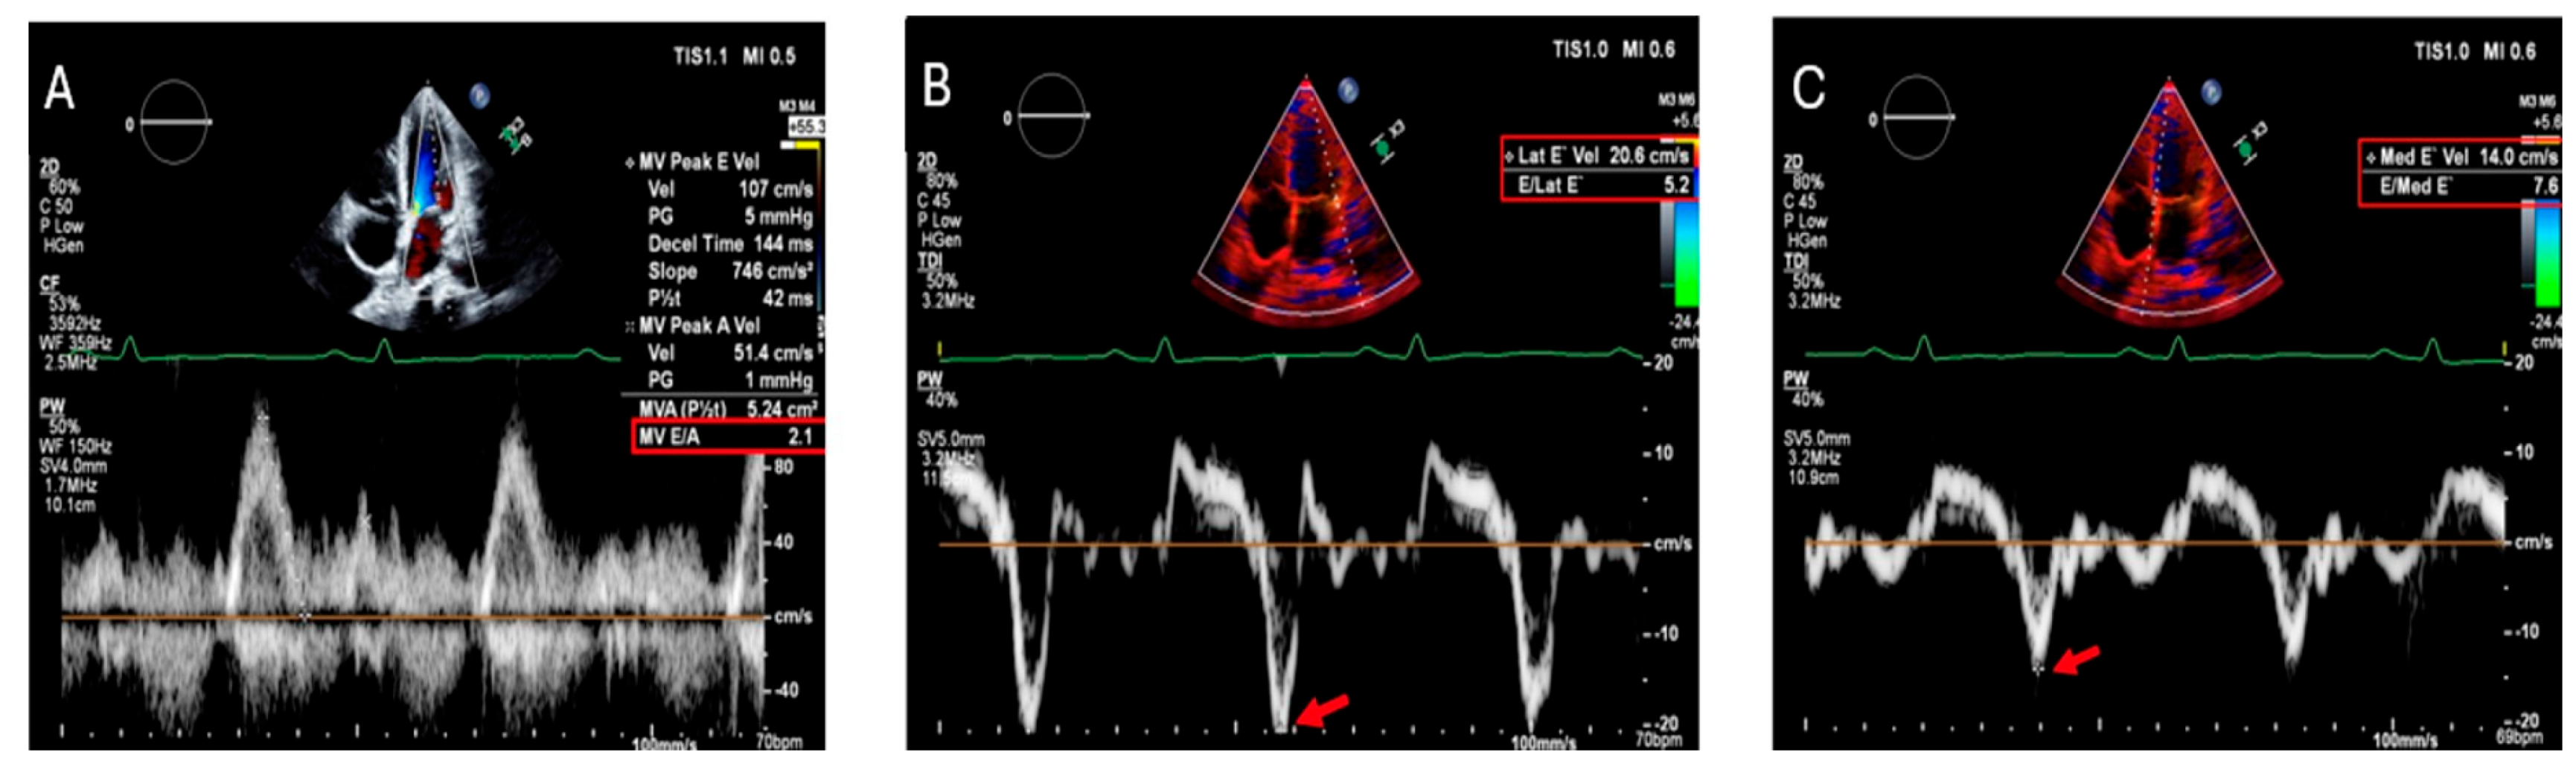

| Echocardiography [81] | Increased wall thickness, diastolic dysfunction | Widely available, non-invasive, first-line imaging, real-time assessment of cardiac function | Limited sensitivity for early iron deposition, operator-dependent, poor tissue characterization |